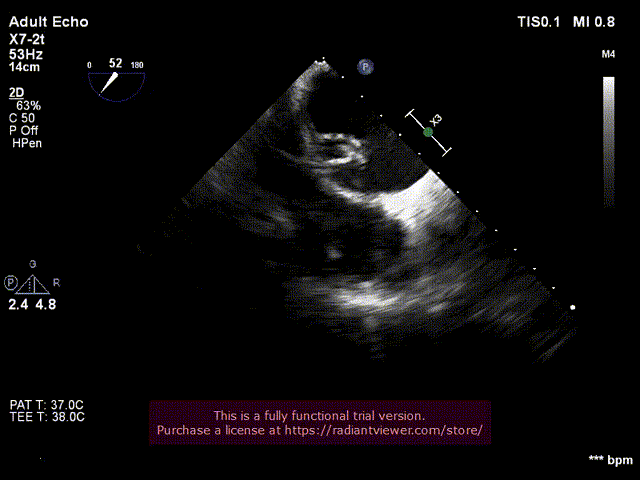

10. 双瓣植入后左室造影与主动脉根部造影

二尖瓣位SAPIEN 3植入后左室造影

双瓣SAPIEN 3瓣膜植入后主动脉根部造影

二尖瓣位和主动脉瓣位SAPIEN 3瓣膜功能良好

二尖瓣位SAPIEN 3瓣膜不影响左室流出道

无心包积液